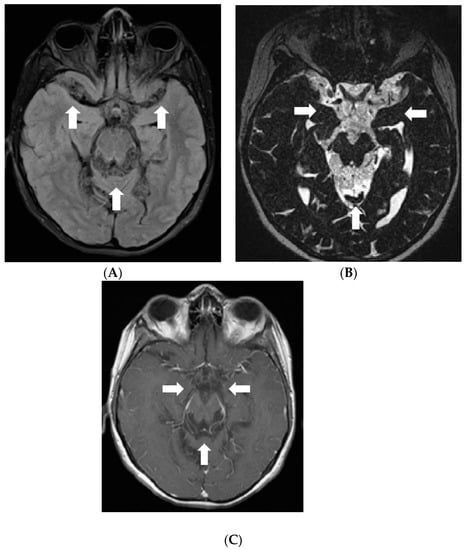

Later the girl was treated in Klaipeda University Hospital. In May 2013, a follow-up MRI demonstrated enlarged cystic lesions in the subarachnoid spaces with compression of the brainstem and the cerebellum and vivid leptomeningeal enhancement extending to the spinal canal (Figure 4). T2W/FLAIR/FS images revealed heterogenous, slightly hyperintense lesions with hypointense foci in the subarachnoid spaces. Clinically, ataxia and weakness of the legs worsened. Partial resection of the neoplastic masses from premedullary cisterns and the IVth ventricle was performed. It was decided to administer chemotherapy with temozolomide. Gradually, the condition of the patient improved.

Figure 4.

Follow-up MRI of the brain 2 years after the onset of symptoms (May 2013): (A) Axial T2W/FLAIR/FS, (B) axial, and (C) sagittal T1W postcontrast images demonstrate enlarged cystic lesions in the subarachnoid spaces causing compression of the brainstem and the fourth ventricle and vivid leptomeningeal enhancement extending to the spinal canal.